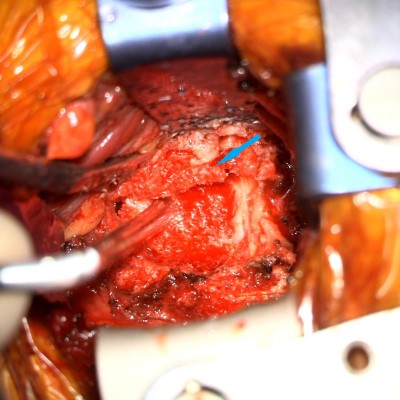

- Intra-op